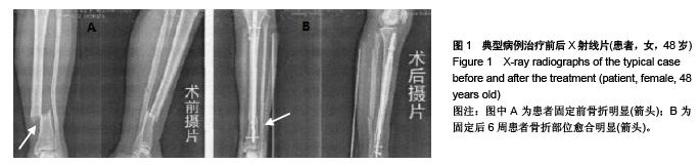

Zhang Zeng-gao, Zhou Xiao-dong, Zhao Qi-ai, Wu Li-wei. Tibial intramedullary nail and locking compression plate repair open tibial fractures by stages: biomechanical characteristics[J]. Chinese Journal of Tissue Engineering Research, 2015, 19(48): 7790-7794.